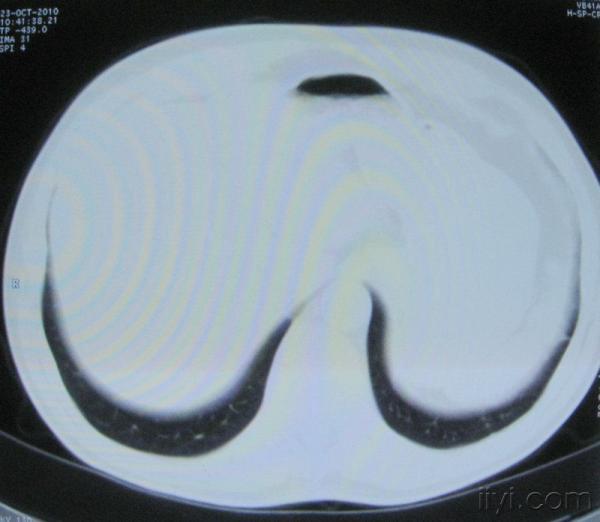

男。60岁,胸片示支气管炎治疗后复查CT。

应该是淋巴结没问题的,中心液化坏死是有这种情况的~~胸科常见到

你指那个肯定是淋巴结,中央系坏死,这很常见,特别在双侧腹股沟会经常看到。这个双侧腋窝及纵隔见多发小淋巴结征。

根据位置考虑应该是淋巴结,密度不均,是因为肿大的淋巴结中心液化坏死